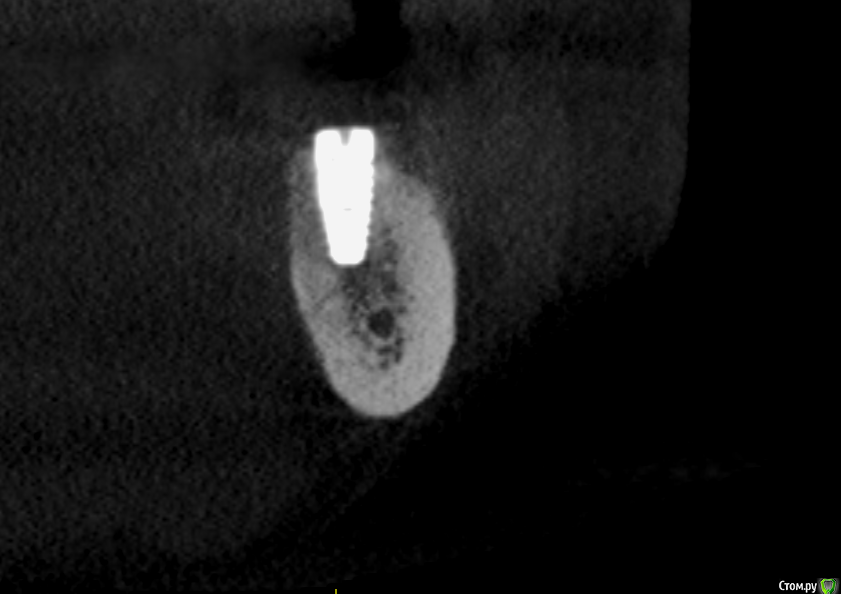

Малик Опубликовано 18 мая, 2016 Поделиться Опубликовано 18 мая, 2016 (изменено) Ровно 3 месяца назад произведена установка имплантата 4.6 с НКР. Заживление первичным натяжением, на момент снятия швов все идеально (К сожалению, нет фоток, не обзавелся еще фотоаппаратом). 2 дня назад позвонила пациентка и сказала, что прям по вершине гребня появилось какое-то образование мягкой консистенции, была назначена на сегодня. Позвонила вчера вечером с жалобой, что данное образование лопнуло, и появилась сукровица. На осмотре определяется свищ по вершине гребня и язычно.Посоветуйте какую тактику предпринять? Раскрыть и поставить формик? И у кого какие мнения по поводу причины этого всего? кт с имплантатом было сделано сегодняP.S. извиняюсь за очень низкое качество фотографий. Изменено 18 мая, 2016 пользователем Малик Ссылка на комментарий

TIGER Опубликовано 19 мая, 2016 Поделиться Опубликовано 19 мая, 2016 Формик с ССТ.Там пришеечная резорбция Ссылка на комментарий

Малик Опубликовано 19 мая, 2016 Автор Поделиться Опубликовано 19 мая, 2016 Формик с ССТ.Там пришеечная резорбцияимплантат биогоризонт,с пришеечной частью Laser-Lok. Ссылка на комментарий

Малик Опубликовано 19 мая, 2016 Автор Поделиться Опубликовано 19 мая, 2016 Я к тому что имплантат был установлен супракрестально,на 1,5мм ( зона лазер лок) выше гребня. Ссылка на комментарий

TIGER Опубликовано 20 мая, 2016 Поделиться Опубликовано 20 мая, 2016 Я к тому что имплантат был установлен супракрестально,на 1,5мм ( зона лазер лок) выше гребня.в этом вся причина...зачем не до глубляли? Ссылка на комментарий

Малик Опубликовано 23 мая, 2016 Автор Поделиться Опубликовано 23 мая, 2016 в этом вся причина...зачем не до глубляли?а зачем? может я чего-то не понимаю, но поверхность лазер лок способствует формированию соединительнотканного соединение. Если заглубить имплантат будет ли интеграция кости в этом месте? ведь сам производитель рекомендует супракрестальную установку Ссылка на комментарий